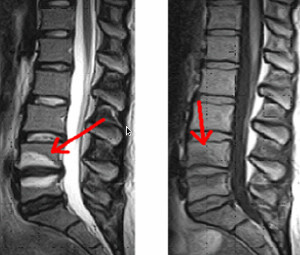

Hernie Discale lombaire

Sténose lombaire